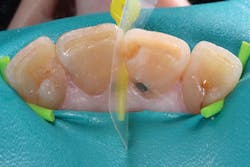

Although the bulk-fill flowable can be placed in larger increments, a small increment was placed first to ensure sufficient curing of the material at the floor of the chamber (figures 3 and 4). The next layer of SureFil SDR flow+ was placed in a 4-mm bulk increment again, followed by 20 seconds of light curing. A final layer of universal composite was placed, occlusion was checked, and after a final polish and postoperative radiograph, the patient was released (figures 5 and 6).